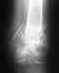

07 марта мама сломала шейку бедра левой ноги и попала в больницу в Подмосковном городе.Маме 81 год, гормонально зависимая астма около 25 лет.От операции врачи воздержались так как, по их словам, ни один анестезиолог не гарантировал исход.Лежала на вытяжке до 17 марта.17 марта наложили легкий гипс, снимок после наложения гипса прилагается.Извиняюсь за качество, на руки снимки не дают, пришлось фото делать на окне.18-марта выписана домой.Так же есть снимки после перелома 7 марта и 9 марта, когда была нога на вытяжке.Что меня тревожит - это положение бедренной кости относительно шейки бедра после наложения гипса.Кость явно смещена вверх.На вытяжке кости располагались близко к друг другу.Может есть смысл снять гипс и снова установить вытяжку?Заранее спасибо всем откликнувшимся.

• Кликните для загрузки файла 18-03-2011 resized.JPG